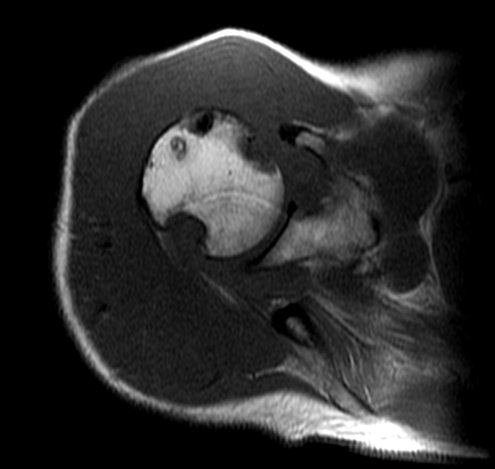

Магнито-резонансная томография левого коленного сустава.

Куницкой О.В. 1978г. от 11.08.2016

На серии аксиальных, коронарных и сагитальных томограмм получены изображения левого коленного сустава. Определяется негомогенность сигнала от гиалинового хряща надколенника и переднихотделов суставной поверхности бедренной кости. Мелкие субхондральный кисты в бедренной и большеберцовой костях. Мениски обычного сигнала. Боковые, крестооборазные связки, собственная связка надколенника не изменены. Синовиальная оболочка неравномрно утолщена. В полости сустава, супрапателлярной сумке, подколенной ямке определяются множественные округлые образования максимальным диаметром 45 мм. с чёткими, неровнымиконтурами, достаточно однородной структуры, гипоинтенсивные во всех типах взвешенности. В полости сустава, супрапателлярной сумке жидкость. Сигнал от мышечных структур окружающих сустав повышен на Т2. При контрастировании определяется усиление сигнала по периферии образований и незначительно самой структурой образований.

Заключение: МРТ-картина диффузного нодулярного синовита левого коленного сустава. Сравнительно со снимками от 02.04.2016 без существенной динамики.

В НИИ им. Петрова в Санкт-Петербурге проанализировав пробы материала после артроскопии (без суставной жидкости) дали другой диагноз: пигментированный виллонодулярный синовит (под вопросом).